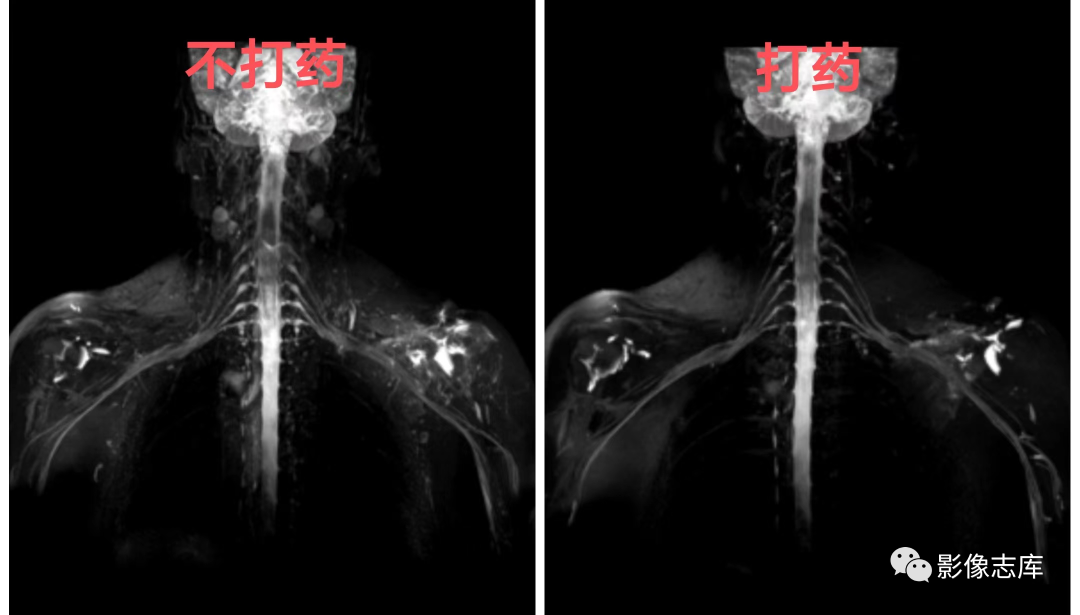

不打药和打药区别:利用重T2结合脂肪抑制STIR序列,可达到一定背景组织抑制的目的,但是血管和淋巴结很难将其抑制,为了达到这些组织不被显现,因此引入打药后的T2负性增强原理,由于微小血管和淋巴结可吸收少量对比剂,对比剂可缩短T2弛豫时间,因此通过打药后的T2加权可达到微小血管和淋巴结抑制的目的。